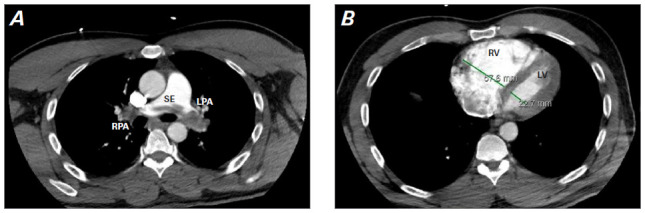

This article reports the case of a 42-year-old man who presented with a saddle pulmonary embolus complicated by normotensive cardiogenic shock. The patient was first stabilized with venoarterial extracorporeal membrane oxygenation. Then, while the patient was still on extracorporeal membrane oxygenation, thrombectomy with a large-bore catheter device was performed that resulted in a large decrease in pulmonary artery pressures and a clinically significant increase in cardiac index, with rapid clinical improvement. Complete recovery of the patient's cardiopulmonary status has been maintained at intermediate-term follow-up. This treatment strategy should be considered favorably in the treatment of patients presenting with pulmonary embolism complicated by cardiogenic shock.